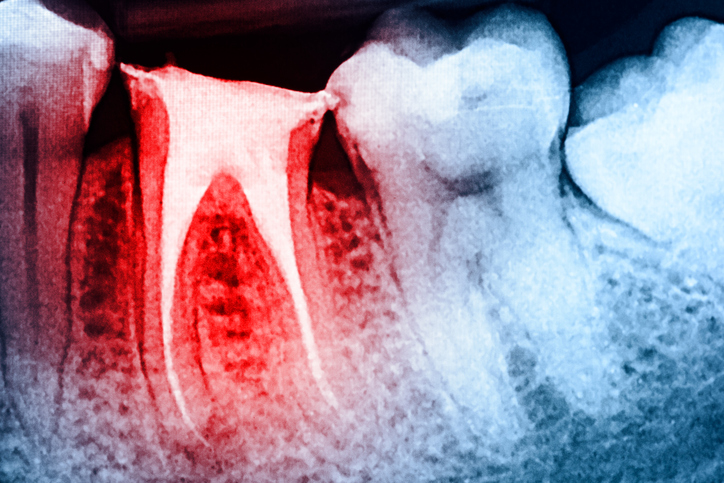

Root canal obturation: Which techniques are most beneficial?

Investigators systematically compared the clinical and radiographic outcomes of different root canal obturation techniques and materials in primary treatments and retreatments.

In a systematic review and meta-analysis, the investigators used data from the PubMed, Cochrane Library and ScienceDirect databases to identify 84 studies examining the clinical and radiographic outcomes in primary root canal treatment and retreatment. They sought to better understand whether certain root canal filling techniques — including warm vertical compaction, warm lateral compaction, cold lateral condensation, single cone and carrier based — could significantly improve endodontic treatment outcomes.

Among the patients who underwent primary root canal treatments, the investigators found no statistically significant differences in the efficacy of the techniques at six, 12 and beyond 36 months of follow-up. However, at 24 months, the cold lateral condensation and carrier-based techniques demonstrated greater treatment success rates compared with the single-cone technique, but these advantages didn’t persist at longer follow-ups. Similarly, among those who underwent root canal retreatments, the single-cone technique resulted in higher success rates compared with cold lateral condensation at 12 months and the carrier-based technique resulted in higher success rates compared with the warm vertical compaction technique at 24 months. There were no statistically significant differences between the cold lateral condensation and carrier-based techniques beyond 36 months.

The investigators emphasized that primary root canal treatment had higher success rates compared with retreatments at most time points. Clinician expertise and case selection appeared to have greater influence over treatment success compared with root canal obturation techniques. Because the certainty of evidence was low to very low and heterogeneity was high, longer-term randomized clinical trials are needed to establish root canal obturation standards.